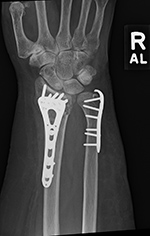

plate and a separate screw), and an oblique angled 3.5 T-plate for fixation of distal radius fractures (figure: wrist T-plate; figure: variable angle volar distal radius locking plate).

53 year-old woman with distal right radial and ulnar fractures. There is an ulnarly applied hook locking compression plate and screws and a variable angle volar distal radius locking plate and screws. |